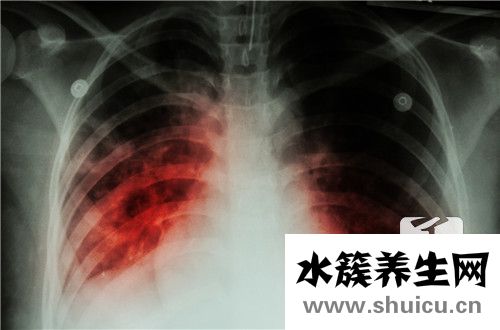

腺病毒肺炎的出現,對患者呼吸系統會造成很大的危害,所以需要及時的確診和治療。腺病毒肺炎的臨床特點主要會有潛伏期,一般是3-8天的時間。感染了腺病毒之后,在兩天的時間就會出現高熱的情況,有大部分...